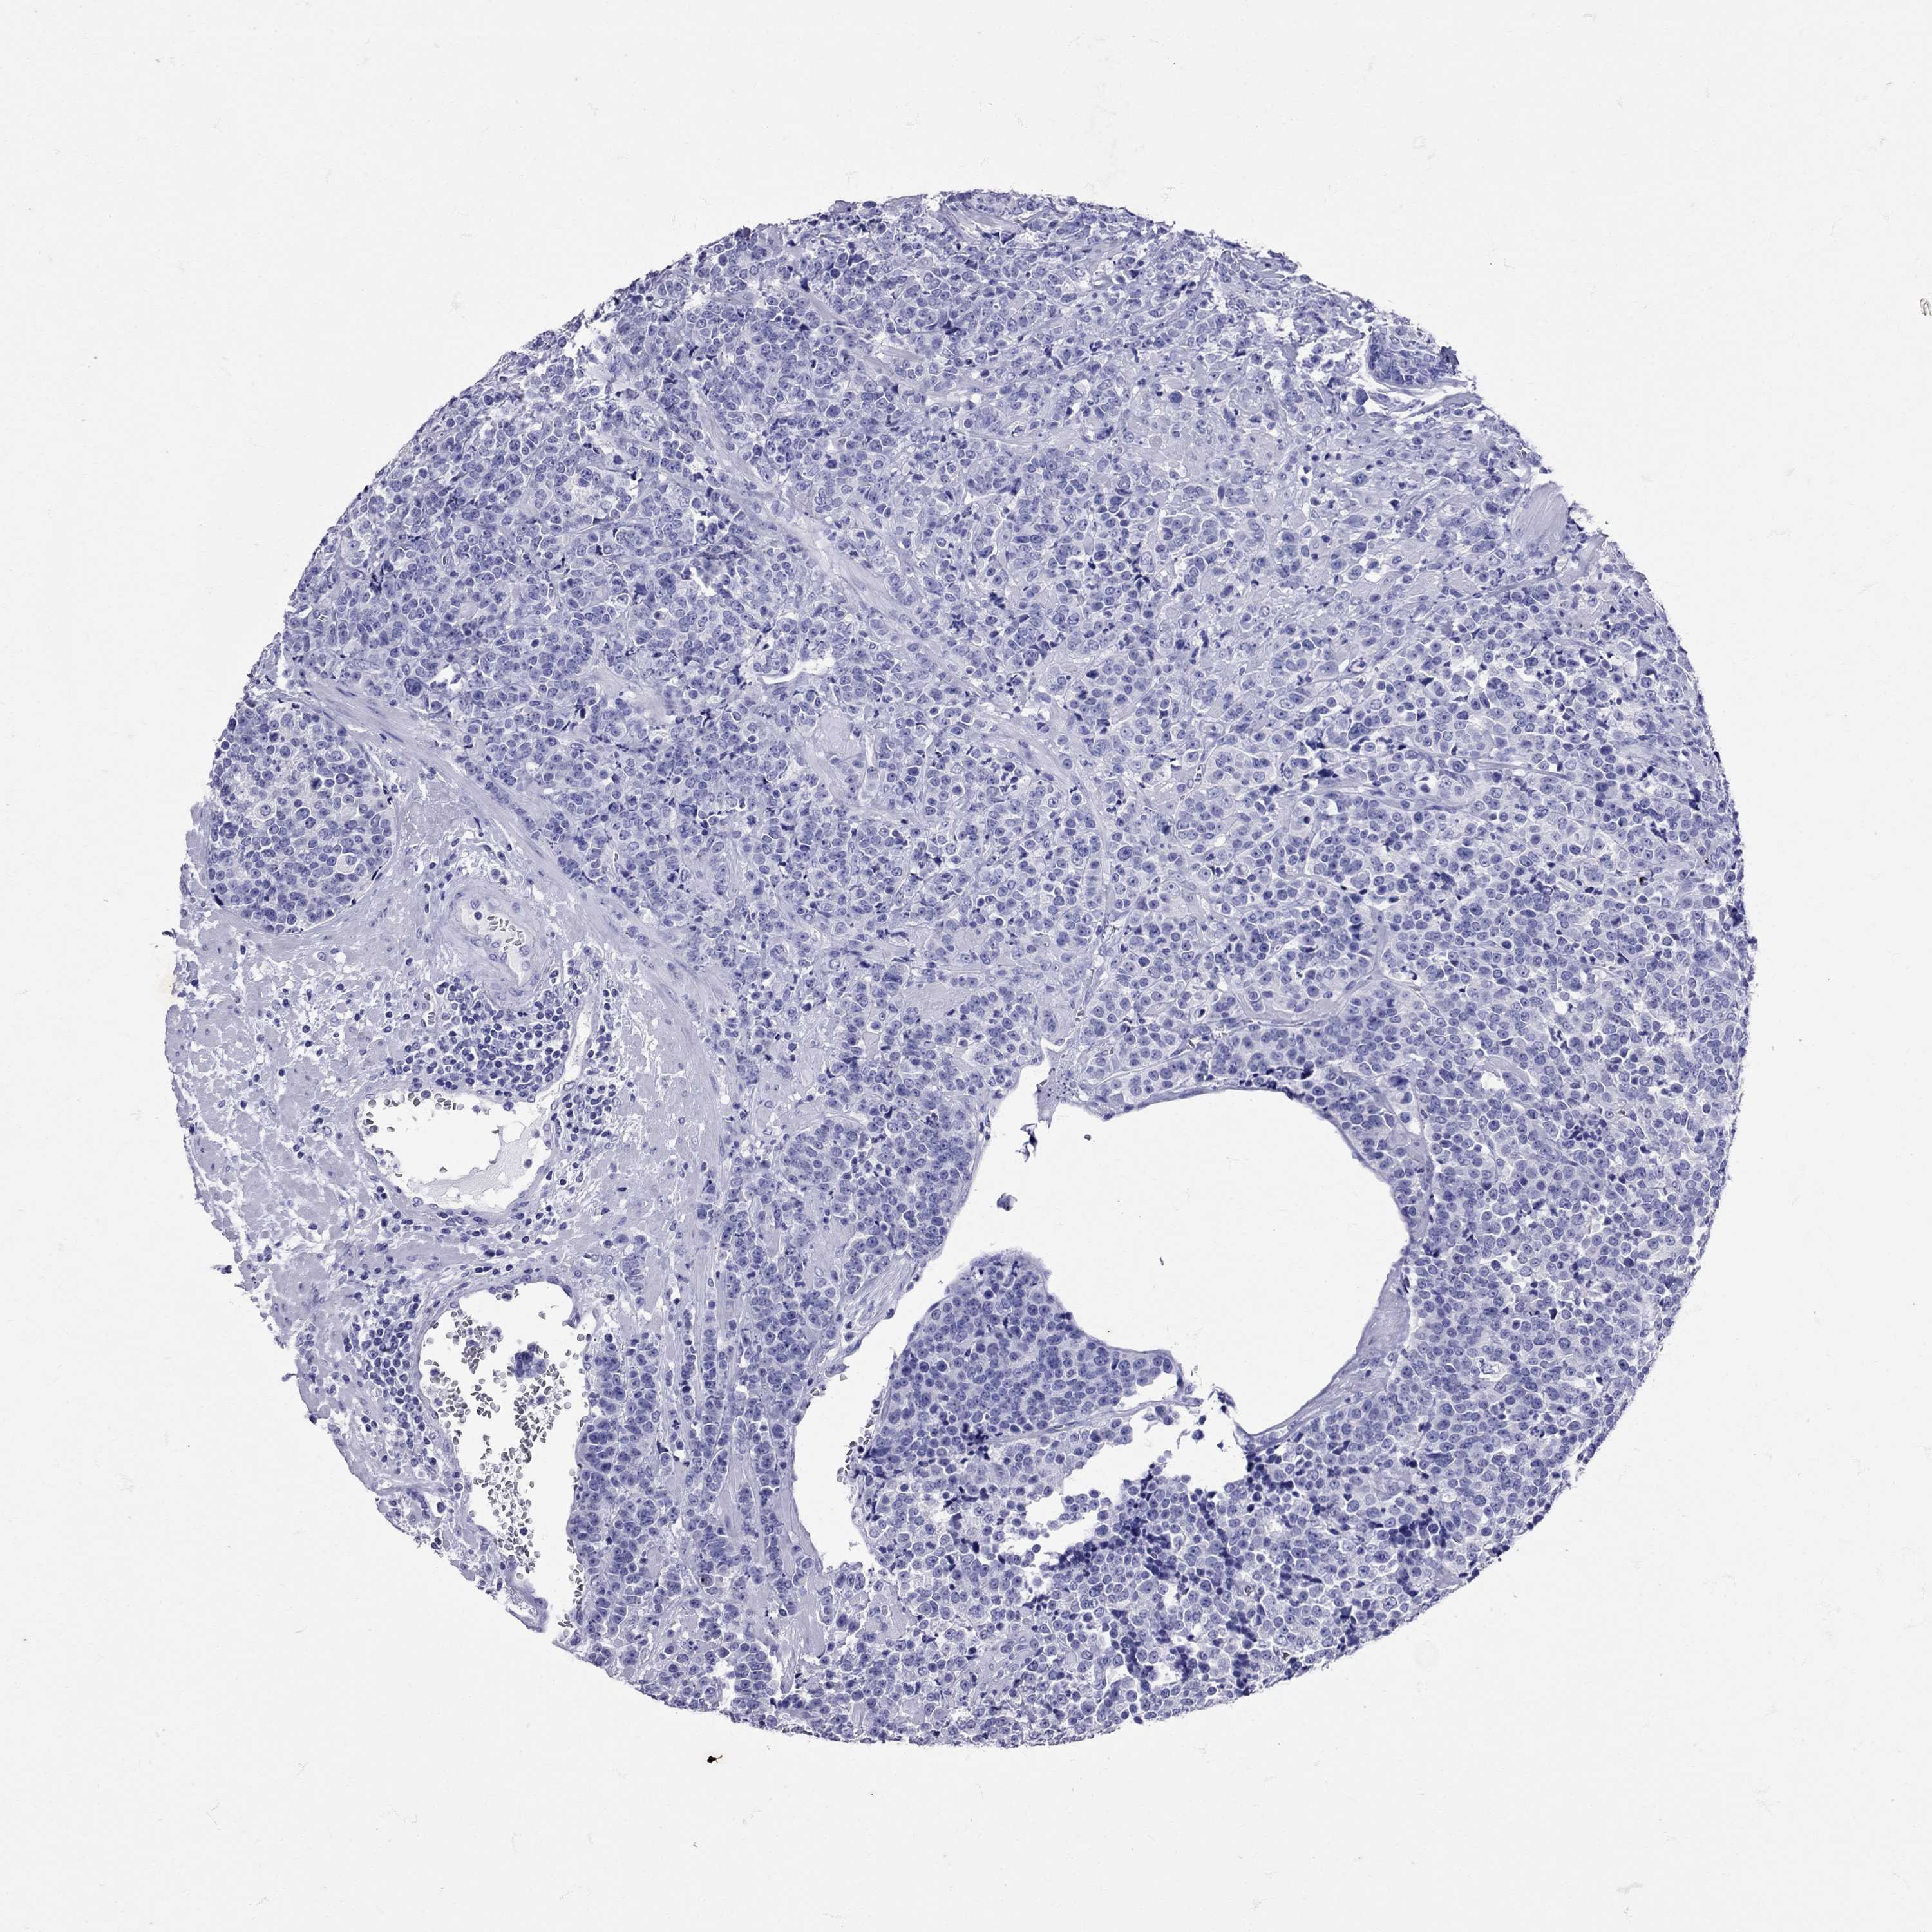

PROSTATE CANCER - Protein expressioni

A mouse-over function shows sample information and annotation data. Click on an image to view it in a full screen mode. Samples can be filtered based on level of antibody staining by selecting one or several of the following categories: high, medium, low and not detected. The assay and annotation is described here.

Note that samples used for immunohistochemistry by the Human Protein Atlas do not correspond to samples in the TCGA dataset.

Antibody stainingi

Antibody staining in the annotated cell types in the current human tissue is reported as not detected, low, medium, or high, based on conventional immunohistochemistry profiling in selected tissues. This score is based on the combination of the staining intensity and fraction of stained cells.

Each image is clickable and will lead to virtual microscopy that enables deeper exploration of all samples and also displays staining intensity scores, fraction scores and subcellular localization as well as patient and tissue information for each sample.

Antibody HPA071892

Antibody CAB025318

Adenocarcinoma, Medium grade

Adenocarcinoma, NOS

Adenocarcinoma, High grade

Adenocarcinoma, Low grade